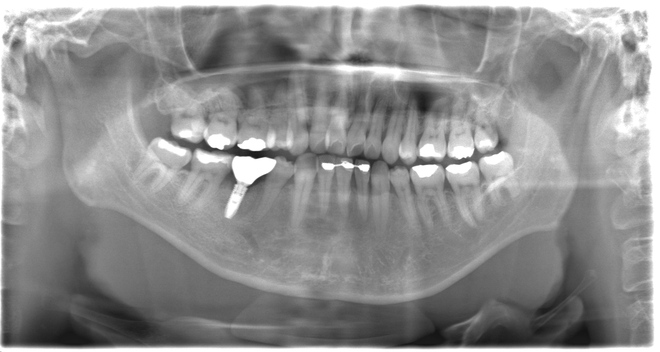

Case02下顎左右6番インプラント(マウスピース矯正を併用)

| 治療期間 | 6ヶ月 |

|---|---|

| 治療費 | インプラント2本1,100,000円 |

| 年齢・性別 | 20代女性 |

| リスクと副作用 | 腫れ、痛み、感染、神経損傷、将来的な脱落 |

| 備考 | 20代女性です。インプラント希望で来院されました。 他院でインプラントを入れるスペースがなく両方の歯を削る必要があると言われ、抵抗があるとのことでセカンドオピニオンで当院に来院されました。 赤坂さくら歯科クリニックオリジナルのインハウスアイライナーのサクライナー矯正で、隙間を閉じた上で一切削らずにインプラントを行いました。 患者様は隙間にものが挟まるストレスからも解放され、とても喜んでらっしゃいました。使用したインプラントはノーベルバイオケア社のインプラントになります。 大臼歯であっても細いインプラントを隙間を矯正などで調整しながら入れることが可能です。 |